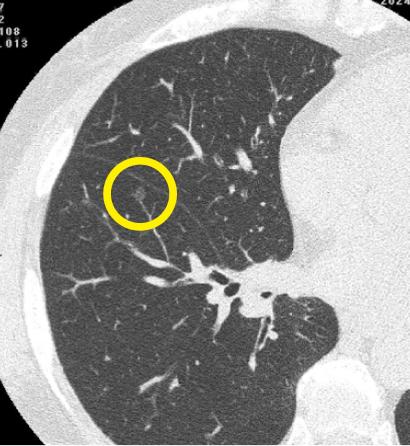

マイシグナル・スキャンを受けて肺がんのリスクが検出された60代のお客さま。精密検査を経て、北海道大学病院呼吸器外科で該当腫瘍を切除する手術を実施し、無事にステージ0の肺がんを取り除くことができました。

レントゲンでは通常映らない、4mm程度の超早期がんのCT画像

マイシグナル・スキャンを受けて肺がんのリスクが検出された60代のお客さま。

精密検査を経て、北海道大学病院呼吸器外科で該当腫瘍を切除する手術を実施し、無事にステージ0の肺がんを取り除くことができました。